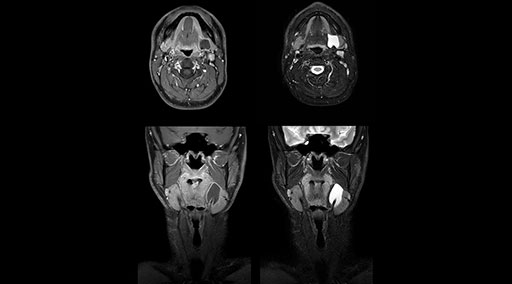

“Our DMG Lisle location includes a cancer center, so soft tissue neck scans, brachial plexus scans, and prostate scans are common. For these exams, mDIXON TSE provides excellent images with and without fat suppression all while helping us reduce repeats and work more efficiently,” Mr. Duffy says.

“With the 2-echo Philips mDIXON TSE the timing is short and the fatsat is very robust. The biggest thing is that you know your fat suppression will be good, even in thin patients or large patients that are off-center,” Mr. Sybesma says.

“Since we work in fixed time slots, not having to repeat scans is key for us,” Mr. Duffy adds. “With mDIXON TSE we get high quality results the first time – unless of course the patient absolutely jumps off the table. For us, that’s significant, because just a single repeat scan could put us behind schedule.

“mDIXON TSE raises our diagnostic confidence with its homogeneous

fat suppression. Neck exams and rheumatology patients are two examples where mDIXON TSE is especially useful,” Dr. Kaakaji says. “For us it’s also an efficiency boost in exams where we need pre and post T1-weighted images with great fat suppression.”